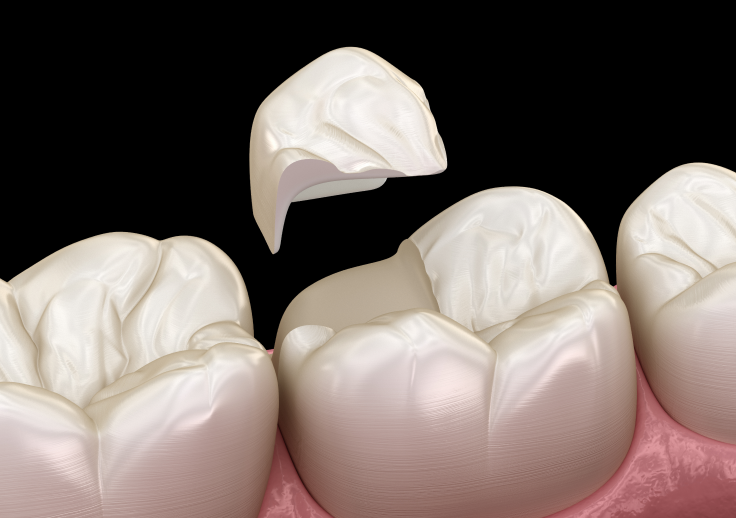

差し歯(クラウン)は、残っている歯の根を土台に人工の歯を被せる治療です。

歯を整え、土台を立てたうえで被せ物を装着します。

・自分の歯の根を活かせる

・見た目や噛む機能を回復できる

ただし、歯の根が弱っている場合や金属の土台を使用すると、

将来的に根が割れるリスクがあるため注意が必要です。

前歯など目立つ部位では、セラミックなど自然な色の素材が選ばれることも多くあります。